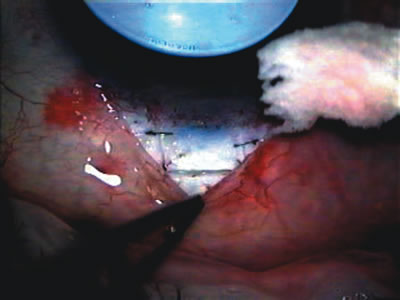

CATARACT EXTRACTION ALONE REDUCES IOP IN MOST EYES WITH ANGLE-CLOSURE GLAUCOMA

Uncomplicated cataract extraction substantially reduces IOP, along with the number of postoperative glaucoma medications in eyes with angle-closure glaucoma.146,147 When preoperative gonioscopy reveals PAS, along with adjacent areas of appositional closure, lens extraction alone in select cases may be a reasonable alternative to filtration surgery.148,149 Phacomorphic angle-closure disease due to enlargement of the lens with progressive angle crowding is eliminated following lens extraction. The width and depth of the anterior chamber angle in eyes with angle-closure glaucoma increases significantly after cataract extraction with IOL implantation and becomes similar to open-angle glaucoma and normal eyes.150,151 (Fig. 5). Combining phacoemulsification, IOL implantation, and limited goniosynechialysis is effective in the treatment of cataract and chronic angle-closure glaucoma.152 Phacoemulsification with implantation of a foldable IOL is more effective in reducing IOP and improving visual acuity than surgical peripheral iridectomy in eyes with acute angle-closure glaucoma.153

Fig. 5. Anterior chamber angle changes associated with lens extraction and PCIOL This 65-year-old Vietnamese woman has a long-standing history of chronic angle-closure glaucoma treated with laser peripheral iridectomy. The optic nerve demonstrated mild glaucomatous damage and IOP was moderately controlled on two antiglaucoma medications. The cataract was removed through temporal clear corneal phacoemulsification with foldable acrylic IOL. A. Symptomatic cataract in narrow-angle glaucoma eye with patent iridectomy. B. Intraoperative goniophotograph showing crowding of angle with increasing narrowness due to phacomorphic component. C. Intraoperative photograph showing temporal clear corneal approach with IOL in the capsular bag. D. Intraoperative goniophotograph demonstrating deepening of chamber angle following lens extraction. Proposed theories for IOP reduction following lens extraction with complete wound closure: